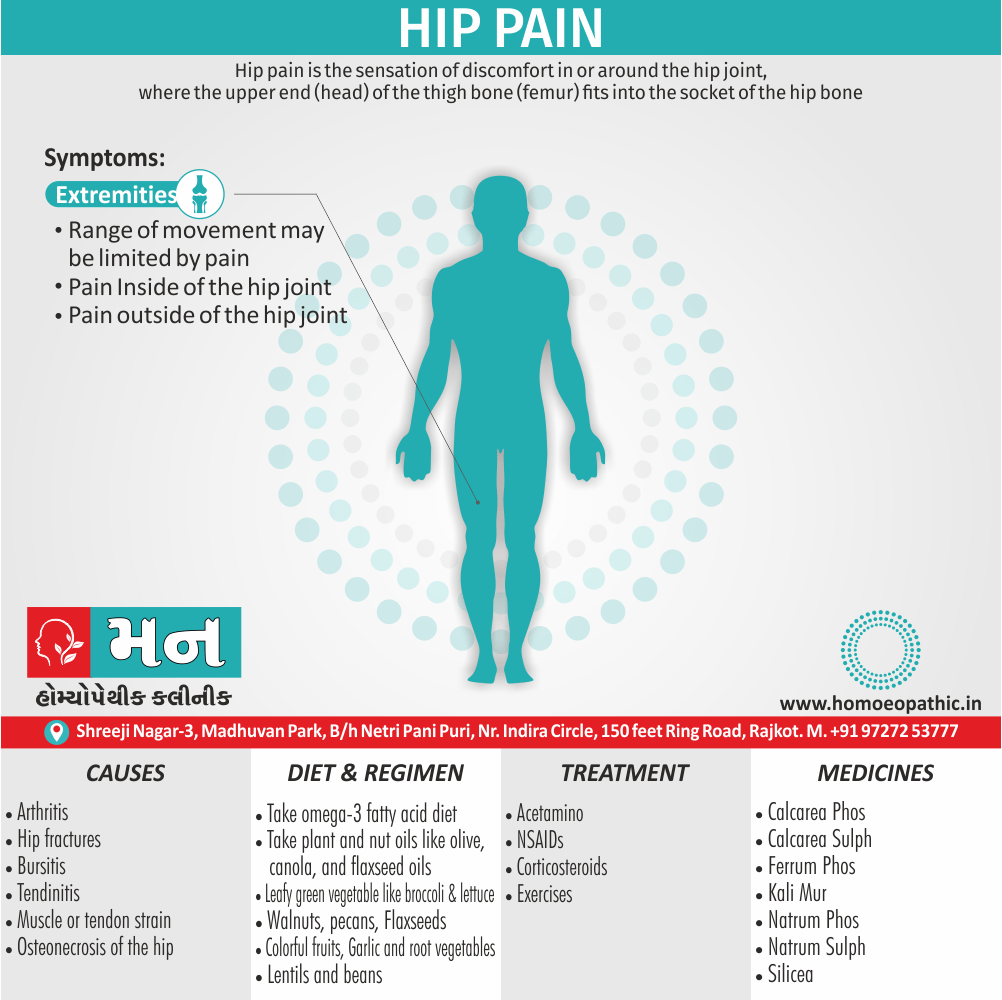

Homeopathic remedies for hip dysplasia best sale

Homeopathic remedies for hip dysplasia best sale, Hip Dysplasia Causing Osteoarthritis Pain in a Cat best sale

Product code: Homeopathic remedies for hip dysplasia best saleHip dysplasia in dogs Joii Pet Care best sale, Hip pain Mann Homeopathy Clinic Rajkot best sale, Amazon Maxwell Pet by Dr.Garber Hip Joint for Dogs The First Natural Biotherapy Supplement Drops to Support and Restore Hip Joint Health Repair and Ease Hip Joint best sale, Homoeopathic Remedies For Arthritis In Dogs Stem Cell Vet best sale, Hip Dyspasia in Dogs best sale, Hip Dysplasia efc homeopathy best sale, Rescue Remedy Natural Homeopathic Stress Relief Drops For Pets 20 ml Amazon Pet Supplies best sale, Homeopathic treatment of Hip Displasia in a Dog by Sarah Stieg DVM MRCVS and Lisa Melling DVM CVH Pitcairn Institute of Veterinary Homeopathy best sale, 8 Simple Home Remedies for Hip Pain Phyiostattva best sale, Rescue Remedy Natural Homeopathic Stress Relief Drops For Pets 20 ml Amazon Pet Supplies best sale, 15 Dog hip dysplasia ideas dog hip dysplasia dog remedies hip dysplasia best sale, Hip Dysplasia In Dogs best sale, Walk Easy Cat Dog Joint Pain Relief Effective Cat Pain Reliever Anti Inflammatory Natural Dog Hip and Joint Supplement Helps with Mobility best sale, Hip Dysplasia in dogs Goel Vet Pharma best sale, Is There a Natural Cure for Hip Dysplasia International Hip Dysplasia Institute best sale, You Can Treat Your Dog s Hip Dysplasia Naturally Healing Paws Center Fort Lauderdale FL best sale, Homeopathic remedies for hip flakier dysplasia in dogs best sale, Amazon T Relief Extra Strength Arthritis Pain Reliever Arnica 12 Natural Medicines for Joint Soreness Stiffness Aches Quick Dissolving Pain Relief for Women Men 100 Tablets Health Household best sale, Developmental Dysplasia of the Hip Homeopathic Remedies best sale, Dog Pain Relief Natural best sale, T Relief Pet Pain Relief Arnica 12 Powerful Natural Medicines Help Reduce Muscle Joint Hip Pain Soreness Stiffness Injuries in Dogs Cats best sale, Top 5 Remedies For Dog Joint Pain And Injury best sale, How To Treat Hip Bursitis Orthobridge Orthopaedic Institute best sale, Buy Dysomin Drops Homeopathic Medicine Doctor Bhargava best sale, JointButter Dr. Dobias Natural Healing best sale, Beyond the Itch Exploring Homeopathic Remedies for Dog Skin Allergies Goel Vet Pharma Pvt. Ltd. Beyond the Itch Effective Homeopathic Remedies for Dog Skin Allergies best sale, Cat Arthritis Meds best sale, How To Treat Hip Bursitis Orthobridge Orthopaedic Institute best sale, Natural Remedies For Hip Dysplasia best sale, Hip Dysplasia and Everyday Life International Hip Dysplasia Institute best sale, Homeo Treatment for Hipdysplasia Hipdysplasia in dogs best sale, Ruta graveolens a useful homeopathic medicine for musculoskeletal disorders ScienceDirect best sale, T Relief Pet Pain Relief Arnica 12 Powerful Natural Medicines Help Reduce Muscle Joint Hip Pain Soreness Stiffness Injuries in Dogs Cats best sale, Hip Dysplasia Causing Osteoarthritis Pain in a Cat best sale, Hip Dyspasia in Dogs best sale.

Homoeopathic Remedies For Arthritis In Dogs Stem Cell Vet- homeopathic remedies for hip dysplasia